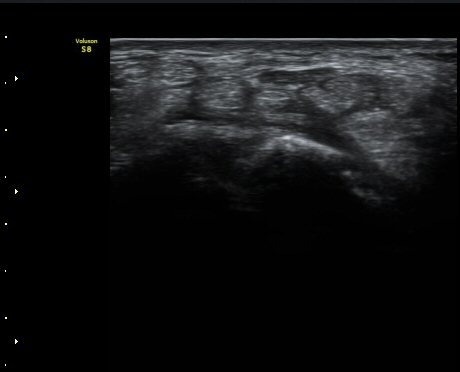

ÃÊÀ½ÆÄ °Ë»ç

¼Õ¸ñ(lunate ±âÁØ)°ú ¼ö±Ù°ü ±ÙÀ§ºÎ(scaphoid ±âÁØ) Á¤Á߽Űæ Ⱦ´Ü¸é°Ë»ç¿¡¼­ Á¤»óÀûÀÎ

¸ð¾çÀ¸·Î °üÂûµÈ´Ù(±×¸² 1, 2).